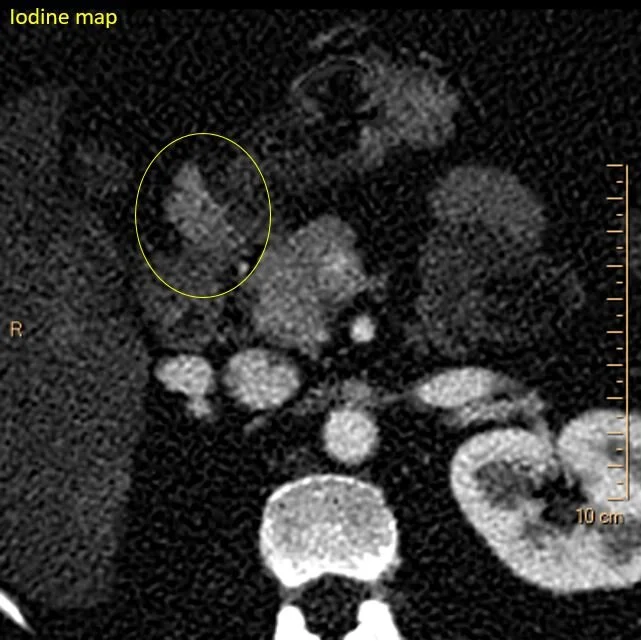

On the lower keV images, there is an intensely enhancing mass at the undersurface of the pylorus/duodenal bulb. This is nicely depicted on the iodine map. On spectral curves, this is identical to the pancreas.

So yes, the pancreas is normal, but there is a small accessory pancreas adjacent to the pylorus/duodenal bulb. This was hiding in plain sight on multiple prior exams, and is nicely seen in retrospect on a previous MRI.

Iodine map shows uptake identical to the pancreas